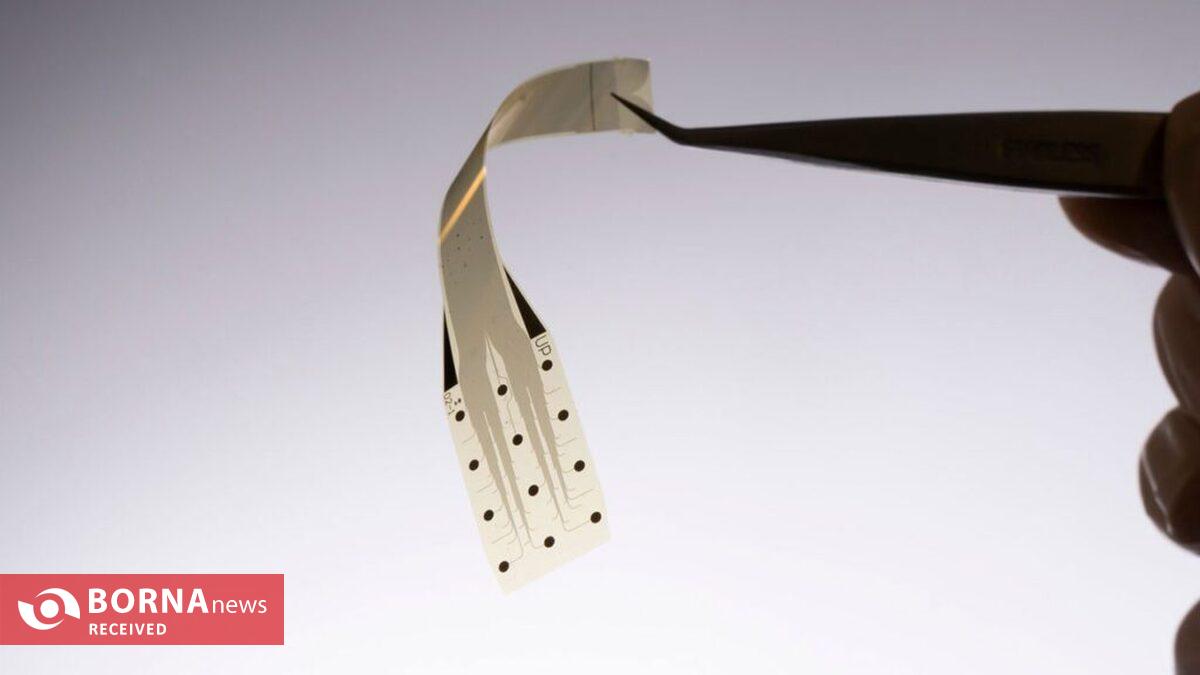

برنا - گروه علمی و فناوری: یک آزمایش بالینی جدید در USC در حال بررسی است که آیا ایمپلنت ی نازکتر از تار مو و ساخته شده از سلولهای بنیادی میتواند سلولهای آسیبدیده شبکیه را جایگزین کرده و بینایی از دست رفته بیماران مبتلا به تحلیل لکهای وابسته به سن را بازگرداند.

برنا - گروه علمی و فناوری: پژوهشگران با کارگذاری ایمپلنت های نرم در جنین قورباغه، موفق به ثبت زندهی رشد مغز از ابتدا تا بلوغ شدند.

برنا - گروه علمی و فناوری: محققان موفق به ساخت یک ایمپلنت انعطافپذیر جدید شدهاند که میتواند سطح شنوایی را در افراد مبتلا به کمشنوایی افزایش دهد.